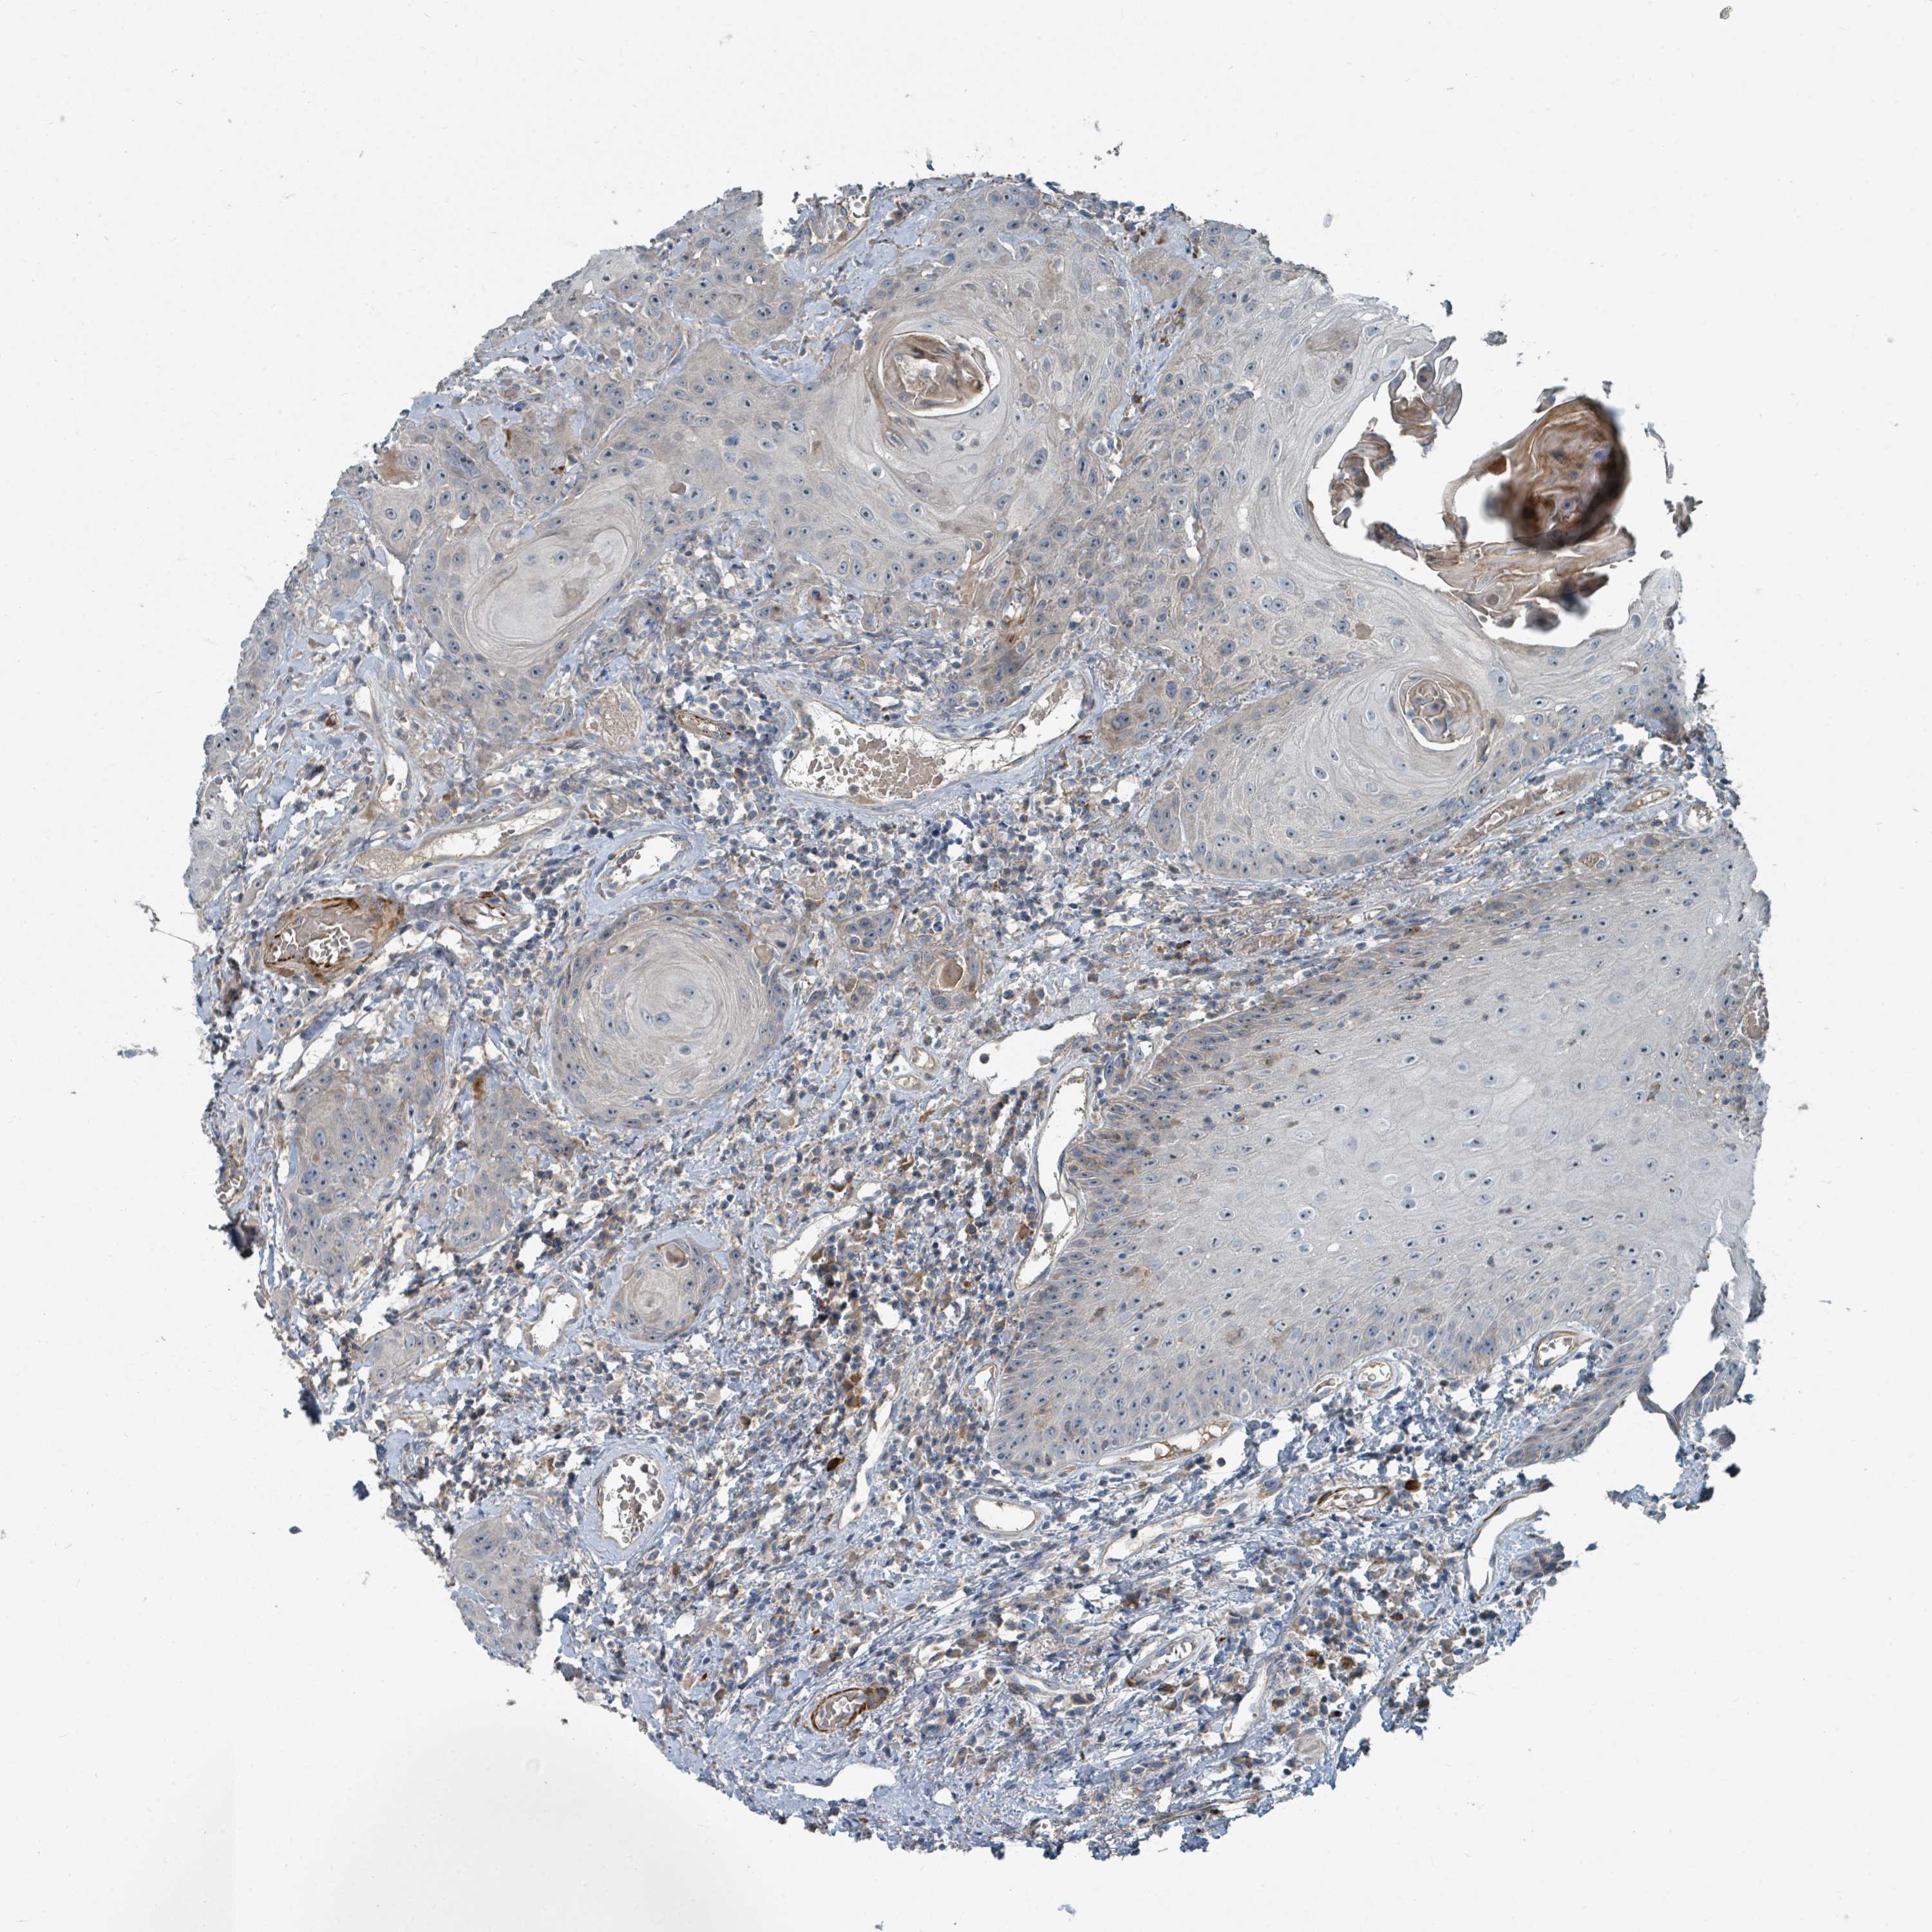

HEAD AND NECK CANCER - Protein expressioni

A mouse-over function shows sample information and annotation data. Click on an image to view it in a full screen mode. Samples can be filtered based on level of antibody staining by selecting one or several of the following categories: high, medium, low and not detected. The assay and annotation is described here.

Antibody stainingi

Antibody staining in the annotated cell types in the current human tissue is reported as not detected, low, medium, or high, based on conventional immunohistochemistry profiling in selected tissues. This score is based on the combination of the staining intensity and fraction of stained cells.

Each image is clickable and will lead to virtual microscopy that enables deeper exploration of all samples and also displays staining intensity scores, fraction scores and subcellular localization as well as patient and tissue information for each sample.

Antibody HPA047455

Antibody HPA051011

Staining

High

Medium

Low

Not detected

Intensity

Strong

Moderate

Weak

Negative

Quantity

>75%

75%-25%

<25%

None

Location

Nuclear

Cytoplasmic/membranous

Cytoplasmic/membranous,nuclear

Adenocarcinoma, NOS

Squamous cell carcinoma, NOS